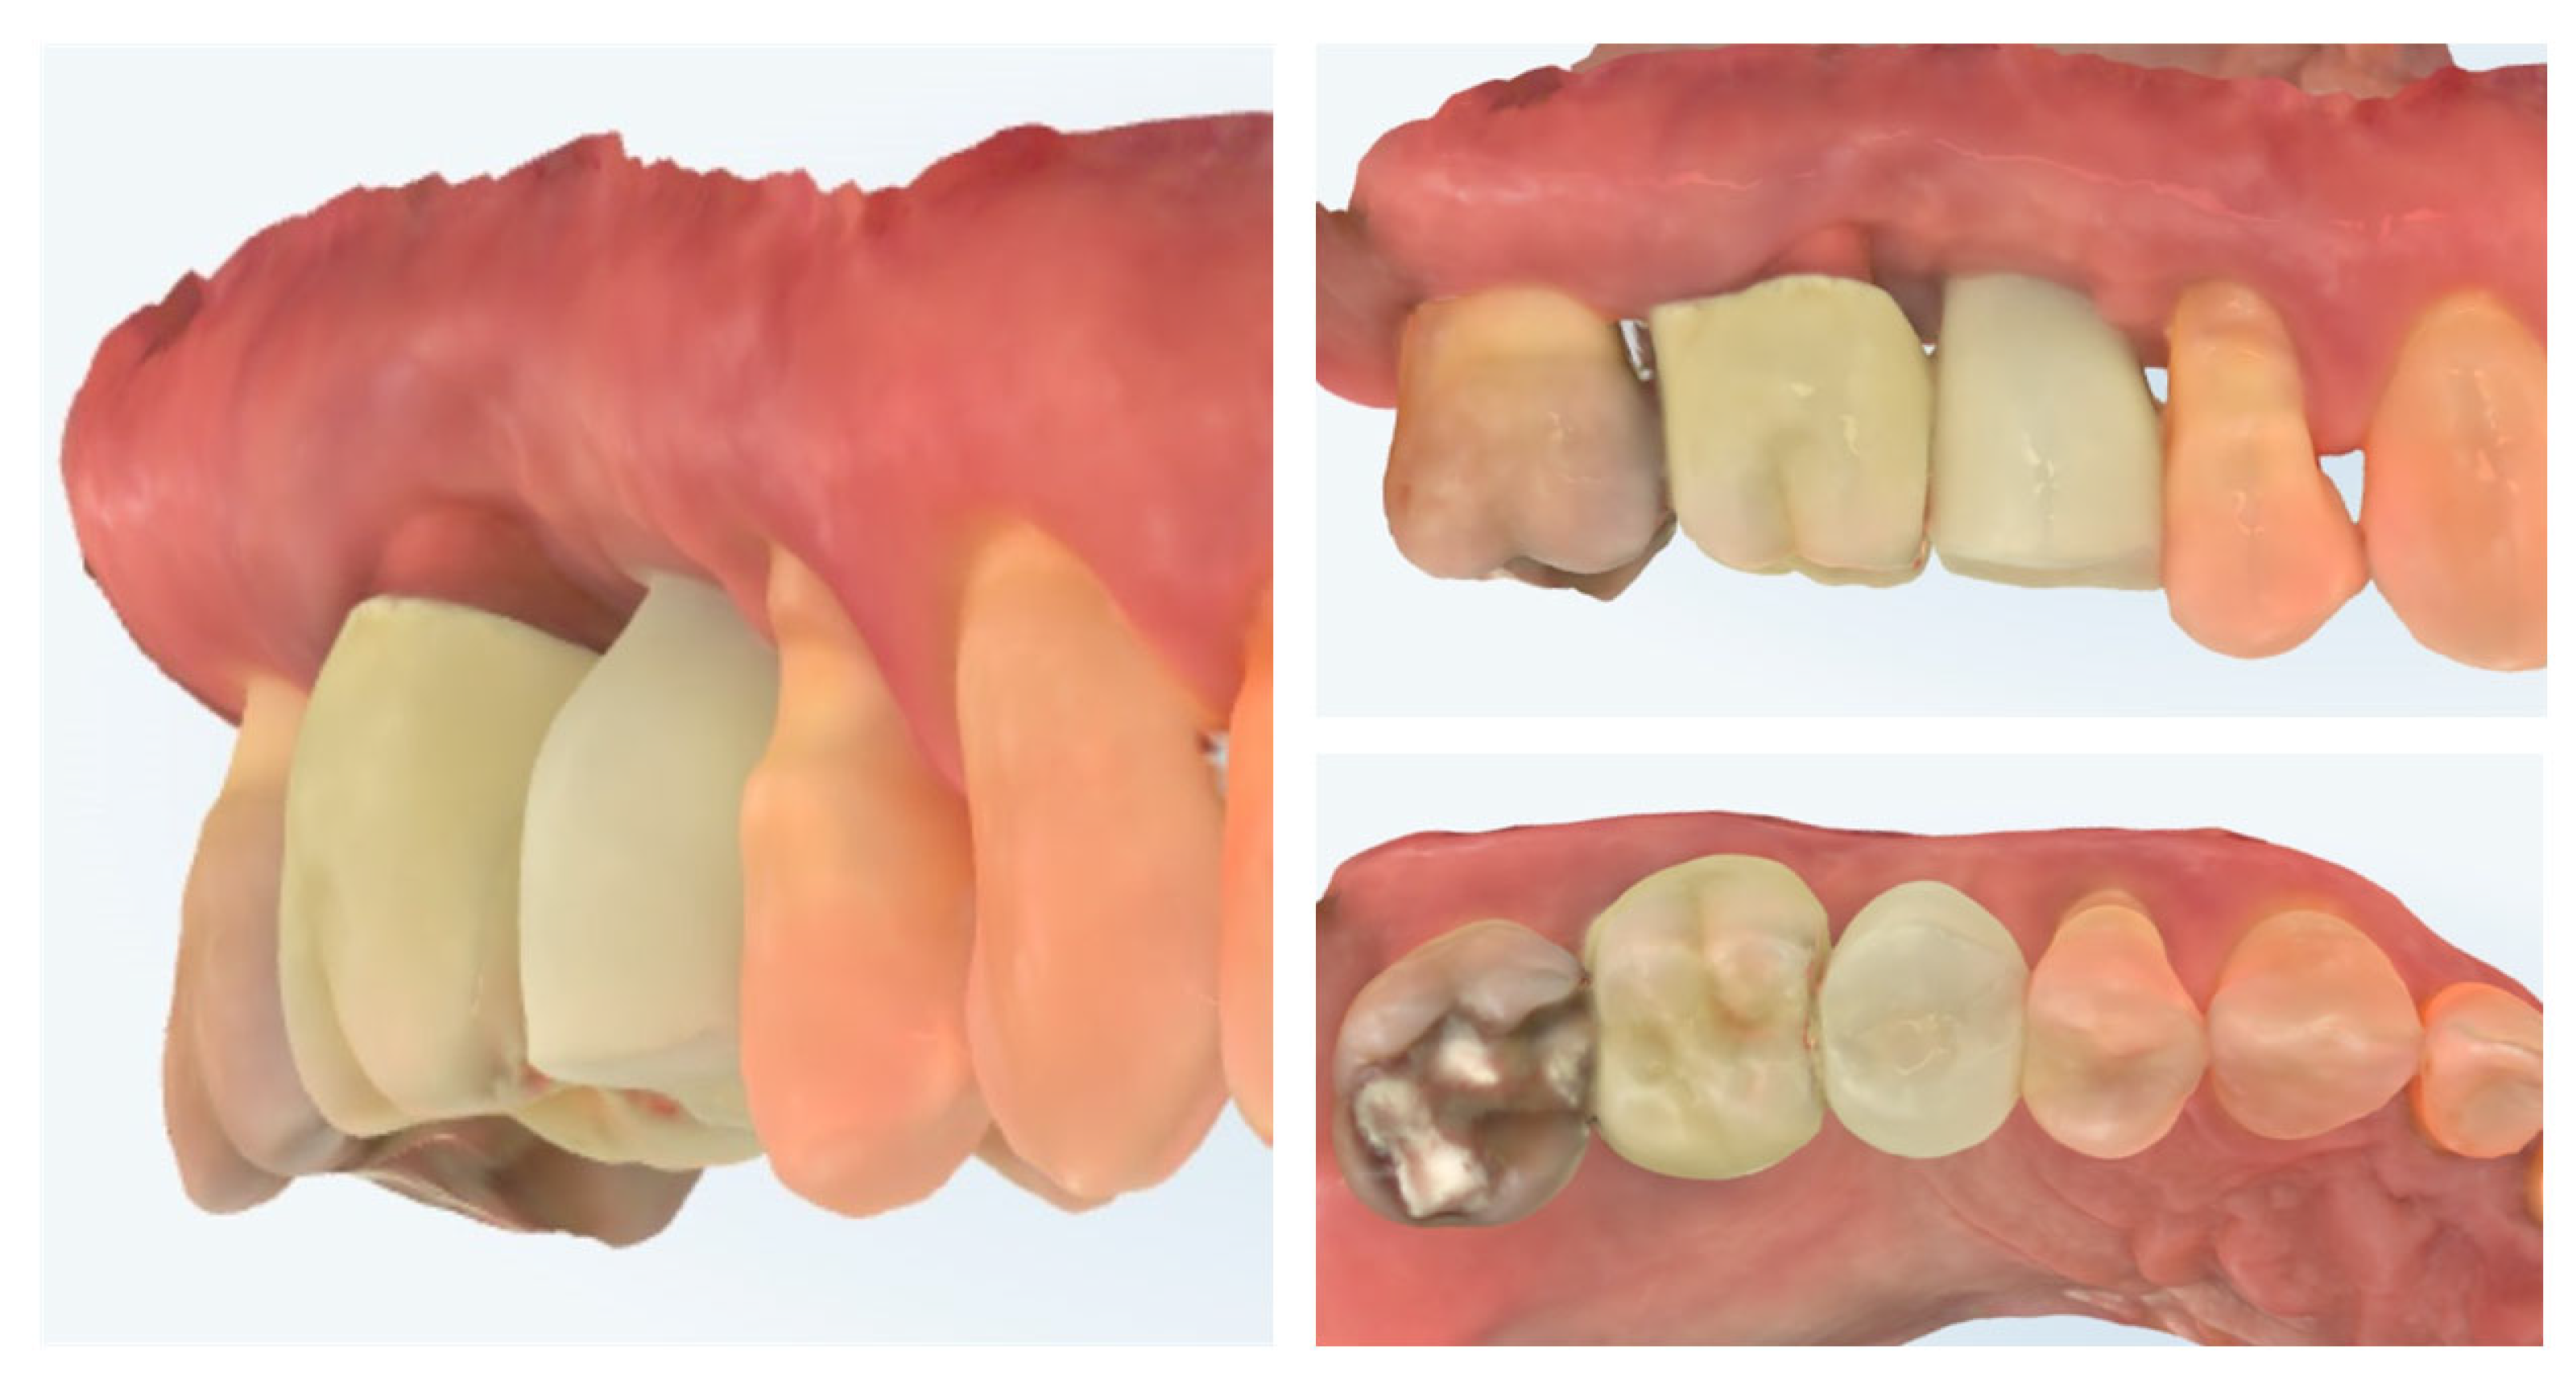

| Timepoint | Horizontal Thickness (mm) | Vertical Thickness (mm) | Clinical/Radiographic Findings | |

|---|---|---|---|---|

| 1 | Baseline (Day 0) | 2.3 | 2.4 | Initial thin buccal tissue |

| 2 | 2 weeks post-op | Uneventful healing, stable mucosal margin | ||

| 3 | 3 months post-op (with provisional) | 3.4 | 3.4 | Increased thickness, stable bone and mucosa |

| 4 | 4 months post-provisional | 3.5 | 3.6 | Stable peri-implant mucosa around provisional crown |

| 5 | 8 months post-op (final crown) | 3.5 | 4.1 | Final crown placed, harmonious soft tissue contours, and stable crestal bone |

| 6 | 14 months post-definitive | Long-term stability of soft tissue and crestal bone confirmed |